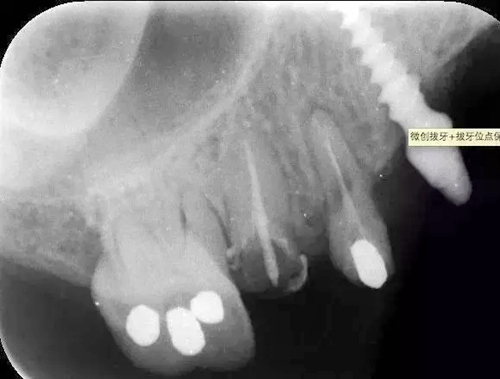

病例:患者,女、44歲,主訴:上頜烤瓷修復(fù)體脫落,要求重新烤瓷修復(fù)。

檢查:14根面旁穿,無法保留,15根長不足。

處理:14、15微創(chuàng)拔牙+拔牙位點(diǎn)保存術(shù)。

?術(shù)前的x線根尖片